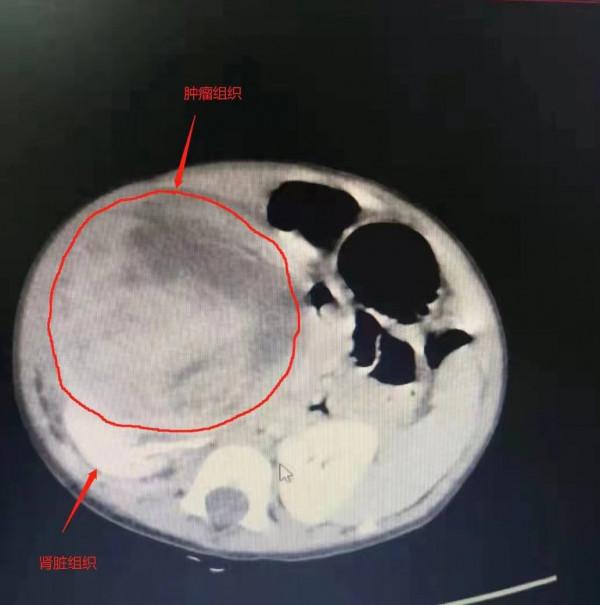

2個多月前,來自湖北荊州10個月大的小語持續低燒。原以為是幼兒普通的發燒感冒,然而幾周治療後,小語的症狀絲毫沒有緩解。行上腹部CT提示:右腎有巨大佔位性病變。一個直徑10釐米的、外形疑似“第三個腎臟”異物,與右腎緊緊地擠在一起。

武漢大學人民醫院泌尿外III科主任程帆教授綜合臨床症狀和影像學檢查,“第三個腎”高度懷疑為腎母細胞瘤腫物。